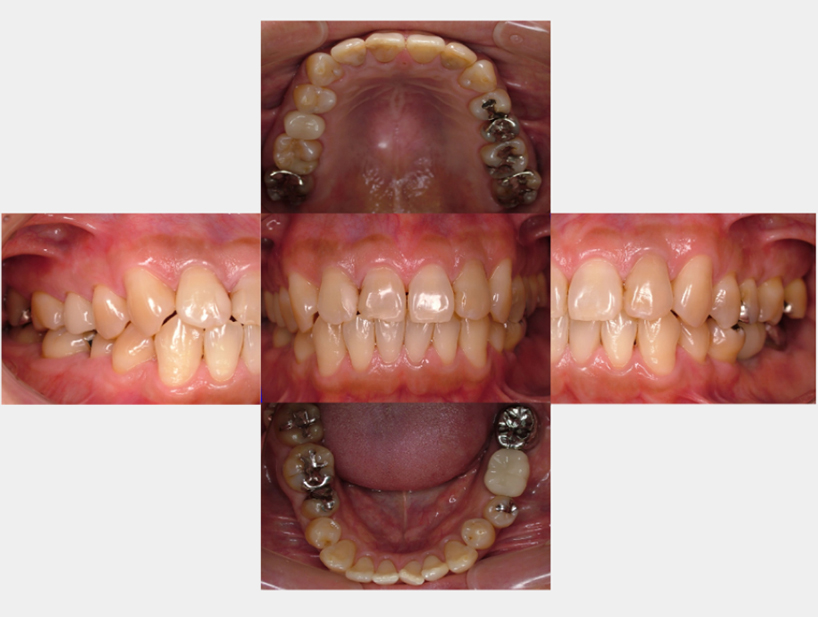

治療前治療後

| 治療内容 | インプラント奥歯1本・根管治療6歯 |

|---|---|

| 患者様の年齢 | 54歳 |

| 患者様の性別 | 女性 |

| 治療期間 | 2年 |

| 治療回数 | 根管治療合わせて70回程度 |

| 治療費用 | インプラント1歯 50万円/根管治療6歯 30万円 |

| 治療で得られるメリット |

|

| 治療する際に起こる リスク・副作用 |